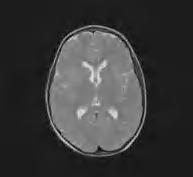

Leukodystrofia z hipomielinizacją oraz zanikiem zwojów podstawy i móżdżku – HLD6 (H-ABC, hypomyelination with basal ganglia and cerebellar atrophy) to ultrarzadka choroba, wywołana dominującymi mutacjami w jednym allelu genu TUBB4. Neuropatologicznie istota biała zawiera jedynie śladowe ilości mieliny i oligodendrocytów oraz reaktywną astroglejozę. Aksony są względnie zachowane. W skorupach i głowach jąder ogoniastych widoczny jest zanik neuronów. W móżdżku obserwuje się zanik warstwy ziarnistej i drobinowej oraz wybiórczo – niektórych komórek Purkinjego. Zmianom tym towarzyszy nasilona reaktywna glejoza astrocytarna i mikroglejowa. W postaci wrodzonej ruchy płodów są słabe; może występować wielowodzie. Dzieci najczęściej od urodzenia są wiotkie, zwłaszcza osiowo, mają oczopląs. Niekiedy wiotkość pojawia się u nich w pierwszych miesiącach życia, a przy tym przejściowo obserwuje się skłonność do ułożenia odgięciowego. Rodzą się z prawidłowymi parametrami urodzeniowymi, jednak z czasem przyrost obwodu głowy jest spowolniony i pojawia się małogłowie wtórne. Po kilku miesiącach dochodzi do narastającego napięcia w kończynach i rozwija się zespół piramidowo-pozapiramidowy z dystonią, rzadziej choreoatetozą i spastycznością, Odruchy głębokie są zdecydowanie wygórowane. W postaciach o późniejszym początku może być błędnie rozpoznawana postać piramidowo-pozapiramidowa mózgowego porażenia dziecięcego. Mogą wystąpić również drgawki. Rozwój umysłowy dzieci z HLD6 najczęściej jest nieprawidłowy. Badanie RM ukazuje rozległą hipomielinizację (ryc. 5.3), przy czym w początkowym okresie choroby stwierdza się postępujący zanik prążkowia (głównie skorup i głów jąder ogoniastych), a na dalszym etapie najczęściej ich zanik. Z czasem zmiany zanikowe obejmują również móżdżek i całe mózgowie. Choroba ma charakter postępujący i, w zależności od ciężkości przebiegu, prowadzi do zgonu w 2. albo 3. dekadzie życia. Leczenia przyczynowego nie ma. Ryzyko dla potomstwa rodziców chorego jest populacyjne.

Rycina 5.3. Leukodystrofia hipomielinizacyjna z zanikiem zwojów podstawy i móżdżku u 15-miesięcznej dziewczynki (HABC, HLD6). Hiperintensywny sygnał całej istoty białej, silniej hiperintensywna zanikająca skorupa. RM T2-zależny.